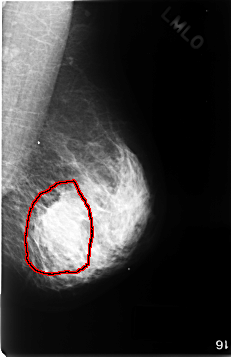

C_0343_1.LEFT_MLO

FILE: C_0343_1.LEFT_MLO.OVERLAY

TOTAL_ABNORMALITIES 1

ABNORMALITY 1

LESION_TYPE MASS SHAPE LOBULATED MARGINS ILL_DEFINED

ASSESSMENT 5

SUBTLETY 4

PATHOLOGY MALIGNANT

TOTAL_OUTLINES 1

BOUNDARY